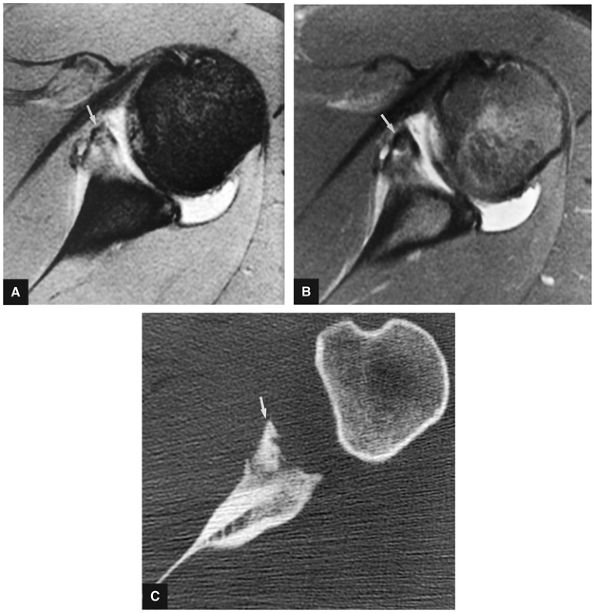

A separate FS PD-weighted FSE sequence is used to increase sensitivity to fluid and to identify paralabral cysts, articular cartilage labral avulsions, and muscle edema (Fig. 8.4). FSE sequences are less sensitive to intralabral signal intensity in the spectrum of degenerations or tears unless there is imbibed fluid. FSE (FS PD FSE) images, however, are superior for the demonstration of labral morphology in cases of avulsions or contour abnormalities.

FIGURE 8.4 ● (A) Axial FS PD FSE image shows intact and congruous humeral head and glenoid articular cartilage surfaces (arrows), separate from the high-signal-intensity intra-articular contrast. (B) PD FSE contrast without FS is shown in an axial image of a Bankart lesion. Chondral surfaces are not as well demonstrated. (C) Excellent contrast is shown between the avulsed anterior labrum and the anterior glenoid rim on the corresponding sagittal FS PD FSE image.